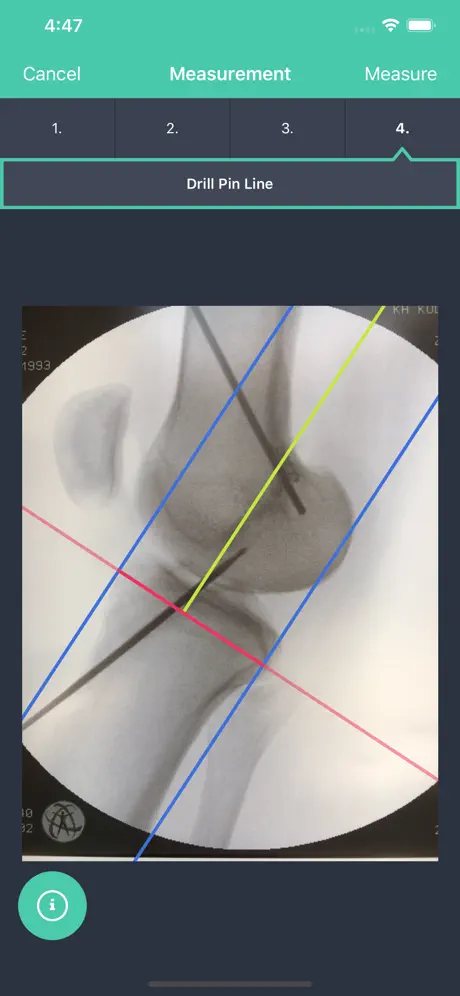

This App was developed for knee surgeons performing anterior cruciate ligament (ACL) reconstruction and using intraoperative fluoroscopy to increase precision of bone tunnel placement.

By means of supporting lines that you can overlay virtually over the X-ray photograph in the app, the app can calculate the relative distance of the target point for the k-wire for a femoral or tibial surgery.

In the medical literature, femoral measurement of a radiographic image is known as quadrant method by Bernard and Hertel. It may help knee surgeons identify the ideal position for bone tunnel placement during ACL reconstruction.

During the operative procedure, place a guide wire (or the tip of an microfracure awl) into the center of the femoral insertion area using your standard operative set up. Alternatively, you may may advance the k-wire in the center of the projected bone tunnel forward penetrating the skin on the lateral side of the femur so the end of the wire is flush with the femoral cortex of the insertion.

The app will display the relative ratio of your target point in reference to the outlines of the bone of the femoral condyles. The measurement values relate to the relative distance of the target point of the most posterior and proximal border of the condyles.

Tibia measurement of a radiographic image has been described by Stäubli und Rauschning. It may help knee surgeons identify the ideal position of the tibial bone tunnel during ACL reconstruction.

Place a guide pin into the center of the projected tibial bone tunnel using a drill guide in a normal fashion. The guide pin may intrude the joint beyond the cortical edge of the ACL footprint.

This app will display the relative distance (in percent) of the entry point of the guide wire into the joint in relation to the total anterior posterior (AP) distance of the proximal tibia (100 %).

This App was developed for knee surgeons performing anterior cruciate ligament (ACL) reconstruction and using intraoperative fluoroscopy to increase precision of bone tunnel placement.

By means of supporting lines that you can overlay virtually over the X-ray photograph in the app, the app can calculate the relative distance of the target point for the k-wire for a femoral or tibial surgery.

In the medical literature, femoral measurement of a radiographic image is known as quadrant method by Bernard and Hertel. It may help knee surgeons identify the ideal position for bone tunnel placement during ACL reconstruction.

During the operative procedure, place a guide wire (or the tip of an microfracure awl) into the center of the femoral insertion area using your standard operative set up. Alternatively, you may may advance the k-wire in the center of the projected bone tunnel forward penetrating the skin on the lateral side of the femur so the end of the wire is flush with the femoral cortex of the insertion.

The app will display the relative ratio of your target point in reference to the outlines of the bone of the femoral condyles. The measurement values relate to the relative distance of the target point of the most posterior and proximal border of the condyles.

Tibia measurement of a radiographic image has been described by Stäubli und Rauschning. It may help knee surgeons identify the ideal position of the tibial bone tunnel during ACL reconstruction.

Place a guide pin into the center of the projected tibial bone tunnel using a drill guide in a normal fashion. The guide pin may intrude the joint beyond the cortical edge of the ACL footprint.

This app will display the relative distance (in percent) of the entry point of the guide wire into the joint in relation to the total anterior posterior (AP) distance of the proximal tibia (100 %).